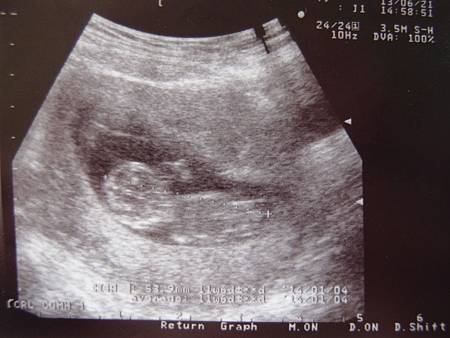

如果沒有因為出血跑醫院照超音波留下難以抹滅的超音波照的話

也把寶寶的超音波照拍下來

6/21  11W5D  第一次正式產檢 領媽媽手冊

今天是第一次正式的國泰產檢,終於可以領到媽媽手冊了,在這之前每一次因為出血做的檢查好像都不能把肚裡的寶寶當作是一個真正的生命一樣,所以今天拿到手冊感覺有點不一樣,我似乎可以開始被稱作媽媽了,但是還是很不真實,今天醫生有做頸部透明帶檢查,厚度0.03cm正常,也看到了鼻骨,沒有唐氏症疑慮,第一次抽血做正式一般產檢,自費$2000多抽一管血做脊髓性肌肉萎縮症的檢查,脊髓性肌肉萎縮症就是俗稱的漸凍人,因為之前聽到老公同事和老婆兩個人抽血都發現竟然有這個基因,那表示肚子裡的寶寶有這個基因的可能性也很大,幸好後來再檢查確定肚子裡的北鼻沒有遺傳到他們的基因,不過也已經嚇得他們只敢生這一胎,不敢再生下一胎了,後來上網查發現有這個基因的發生率也很高,所以即使是自費也得檢查讓自己安心才行啊!今天肚子有較和緩沒有這麼緊緊的感覺了,不過躺著時偶爾會因為脹氣食物差點吐出來都哽在喉頭了,不舒服